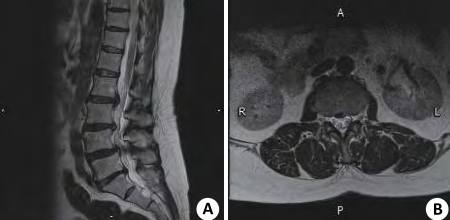

図3:腰椎分離症mri 初期 骨の白い部分が多く重症例だが初期。治癒が十分見込める像。 図4:腰椎分離症mri 軽症例 白い部分が少なく、進行期と判断された例。 ※mriでの腰椎。図3が腰椎分離症重度例。骨の白い部分が濃く出ている。 ②腰椎分離症の診断は、単純x線検査・mri検査・ct検査にて行われる。 ③腰椎分離症の治療は、安静と硬性体幹装具の着用が基本。 ④腰椎分離症のリハビリテーションは腰椎へのストレス軽減を目的に行う。 腰椎分離症とは? 小田菜南子 VICTORYクリニック第二回「子どもと膝」:MRI検査で中学世代の約6割が腰椎分離症の初期段階の兆候も! 競技人生の長さは幼少期が影響。 「止める」勇気で子どもの体を守れ すべての運動の土台となる膝の関節を守る方法について、関節

腰椎分離症 7(ct画像) 初診時 早期に見つかった分離症。 ctでは、まだ分離かどうかはっきりしません。 同左 2カ月後(ct画像) 腰痛がとれたので、すぐに運動を始めてしまいました。 分離の骨折線が分離症発生の病態を把握するため、超初期・初期分離症患者28名(男性25名、女性3名、平均年齢は141歳 )のMRI初診時 MRIのSTIR像を参考に、高輝度変化 (HSC High Signal Change)の広がりを解析したので報告する。Fig 5 初期分離症の sagittal reconstruction CT 画像 分離症は常に pars 尾側から発症する Case 1 Case 2 Case 3 Fig 7 発育期分離症の CT での病期分類 hair line clear gap pseudoarthrosis Early Progressive Terminal direction of maximum principal L5 +1285e+02 S, Max Principal (Avg 75%) +8000e+01 +7

A Lumbar Spine Magnetic Resonance Imaging Scan Of A 15 Year Old High Download Scientific Diagram